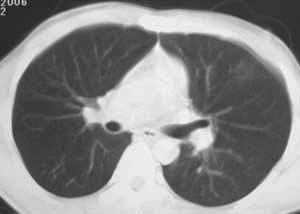

该病灶在纵隔窗没有显示,说明是渗出性病变,而且肺窗看起来也显得它非常淡薄。能造成锁骨骨折,说明受伤时所受冲击力不小。在大冲击力的情况下,胸部发生碰撞的机会非常大,很多患者在受伤后都说不清自己究竟是怎么着地以及究竟是何种姿势受伤。

没有详细的病史,影象上是渗出性改变,中心病灶有空洞存在结核  湿肺 都有可能,那肺泡癌可以除外吗?

有明确的外伤史,病灶呈渗出性改变,密度较低,边缘呈晕圈状改变,周围未见明显的异常血管影及纤维索条影和卫星灶。所以考虑是创伤性湿胸。

左肺上叶前段磨玻璃样结节,中心可见小结节样高密度影及空泡影,我个人觉得首先考虑恶性结节,结合病史,不能完全排除肺挫伤!建议薄层扫描后多方位重建,观察与支气管关系;定期复查,追踪观察(此类病变可能很长时间内不会发生改变),如果结节样高密度成分增多,建议手术切除.